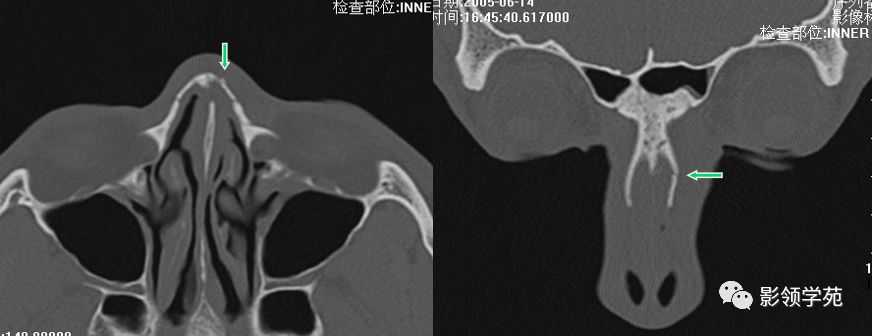

双侧鼻骨骨折

双侧上颌骨额突骨折

鼻中隔骨折